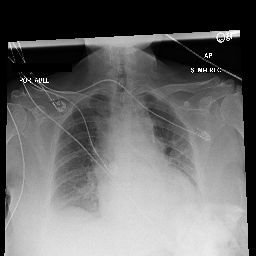

[Uncaptioned image] cardiomegaly is moderate. bibasilar atelectasis is mild. there is no pneumothorax. a lower cervical spinal fusion is partially visualized. healed right rib fractures are incidentally noted. ap portable upright view of the chest. there is no focal consolidation, effusion, or pneumothorax. the cardiomediastinal silhouette is normal. imaged osseous structures are intact. pa and lateral views of the chest. there is mild enlargement of the cardiac silhouette. there is no pleural effusion or pneumothorax. there is no acute osseous abnormalities.

[Uncaptioned image] as compared to the previous radiograph, the monitoring and support devices are unchanged. unchanged bilateral pleural effusions, with a tendency to increase, and resultant areas of atelectasis. the air collection in the bilateral soft tissues is slightly decreased. unchanged right picc line. no definite evidence of pneumothorax. as compared to the previous radiograph, the patient has received a nasogastric tube. the course of the tube is unremarkable, the tip of the tube projects over the middle parts of the stomach. there is no evidence of complication, notably no pneumothorax. the other monitoring and support devices are constant. constant appearance of the cardiac silhouette and of the lung parenchyma. as compared to the previous radiograph, there is no relevant change. tracheostomy tube is in place. there is a layering pleural effusions. NAME bilateral pleural effusion and compressive atelectasis at the right base. there is no pneumothorax.

[Uncaptioned image] the course of the dobbhoff feeding catheter is unremarkable, and its tip is seen projecting over the stomach. there is no evidence of complications, specifically no pneumothorax. as compared to the prior radiograph dated DATE, there has been no other significant interval change. ap portable upright view of the chest. overlying ekg leads are present. there is no focal consolidation, effusion, or pneumothorax. the cardiomediastinal silhouette is normal. imaged osseous structures are intact. as compared to the previous radiograph, there is no relevant change. the endotracheal tube terminates approximately 3 cm above the NAME. the endotracheal tube extends into the stomach. there is no evidence of complications, notably no pneumothorax. there is no pleural effusion or pneumothorax.

[Uncaptioned image] interval placement of a left basilar pigtail chest tube with improving aeration in the left mid to lower lung and near complete resolution of the pleural effusion. there are residual patchy opacities within the left mid and lower lung as well as at the right base favoring resolving atelectasis. no pneumothorax is appreciated on this semi upright study. heart remains stably enlarged. mediastinal contours are stably widened, although this NAME be related to portable technique and positioning. this can be better evaluated on followup imaging. no pulmonary edema. as compared to the previous radiograph, the patient has been extubated. the nasogastric tube is in unchanged position. the lung volumes remain low. moderate cardiomegaly with minimal fluid overload but no overt pulmonary edema. no larger pleural effusions. no pneumonia. ap upright and lateral views of the chest. there is moderate cardiomegaly. there is no pleural effusion or pneumothorax. there is no acute osseous abnormalities.

Table 4: Sample images along with ground truth and generated reports. Note that upper case tokens are results of anonymization.

Table 4 demonstrates the qualitative results of our full model. In general, our models are able to generate descriptions that align with the logical flow of reports written by radiologists, which start from general information (such as views, previous comparison), positive, then negative findings, with the order of lung, heart, pleura, and others. TieNet also generates report descriptions with such logical flow but in slightly different orders. For the negative findings cases, both our model and TieNet do well on generating reasonable descriptions without significant errors. Regarding the cases with positive findings, TieNet and our full model both cannot identify all radiological findings. Our full model is able to identify the major finding in each demonstrated case. For example, cardiomegaly in the first case, pleural effusion, and atelectasis in the second case.

A formerly practicing clinician co-author reviewed a larger subset of our generated reports manually. They drew several conclusions. First, our full model tends to generate sentences related to pleural effusion, atelectasis, and cardiomegaly correctly—which is aligned with the clinical finding scores in Table 3. TieNet instead misses some positive findings in such cases. Second, there are significant issues in all generated reports, regardless of the source model, which include the description of supportive lines and tubes, as well as lung lesions. For example, TieNet is prone to generate nasogastric tube mentions while our model tends to mention tracheostomy or endotracheal tube, and yet both models have difficulty identifying some specific lines such as chest tube or PICC line. Similarly, both systems do not generate the sentence with positive lung parenchymal findings correctly.

From this (small) sample, we are unable to draw a conclusion whether our model or TieNet truly outperforms the other since both present with significant issues and each has strengths the other lacks. Critically, neither of them can describe the majority of the findings in the chest radiograph well, especially for positive cases, even if the quantitative metrics demonstrate the reasonable performance of the models. This illustrates that significant progress is still needed in this domain, perhaps building on the directions we explore here before these techniques could be deployed in a clinical environment.